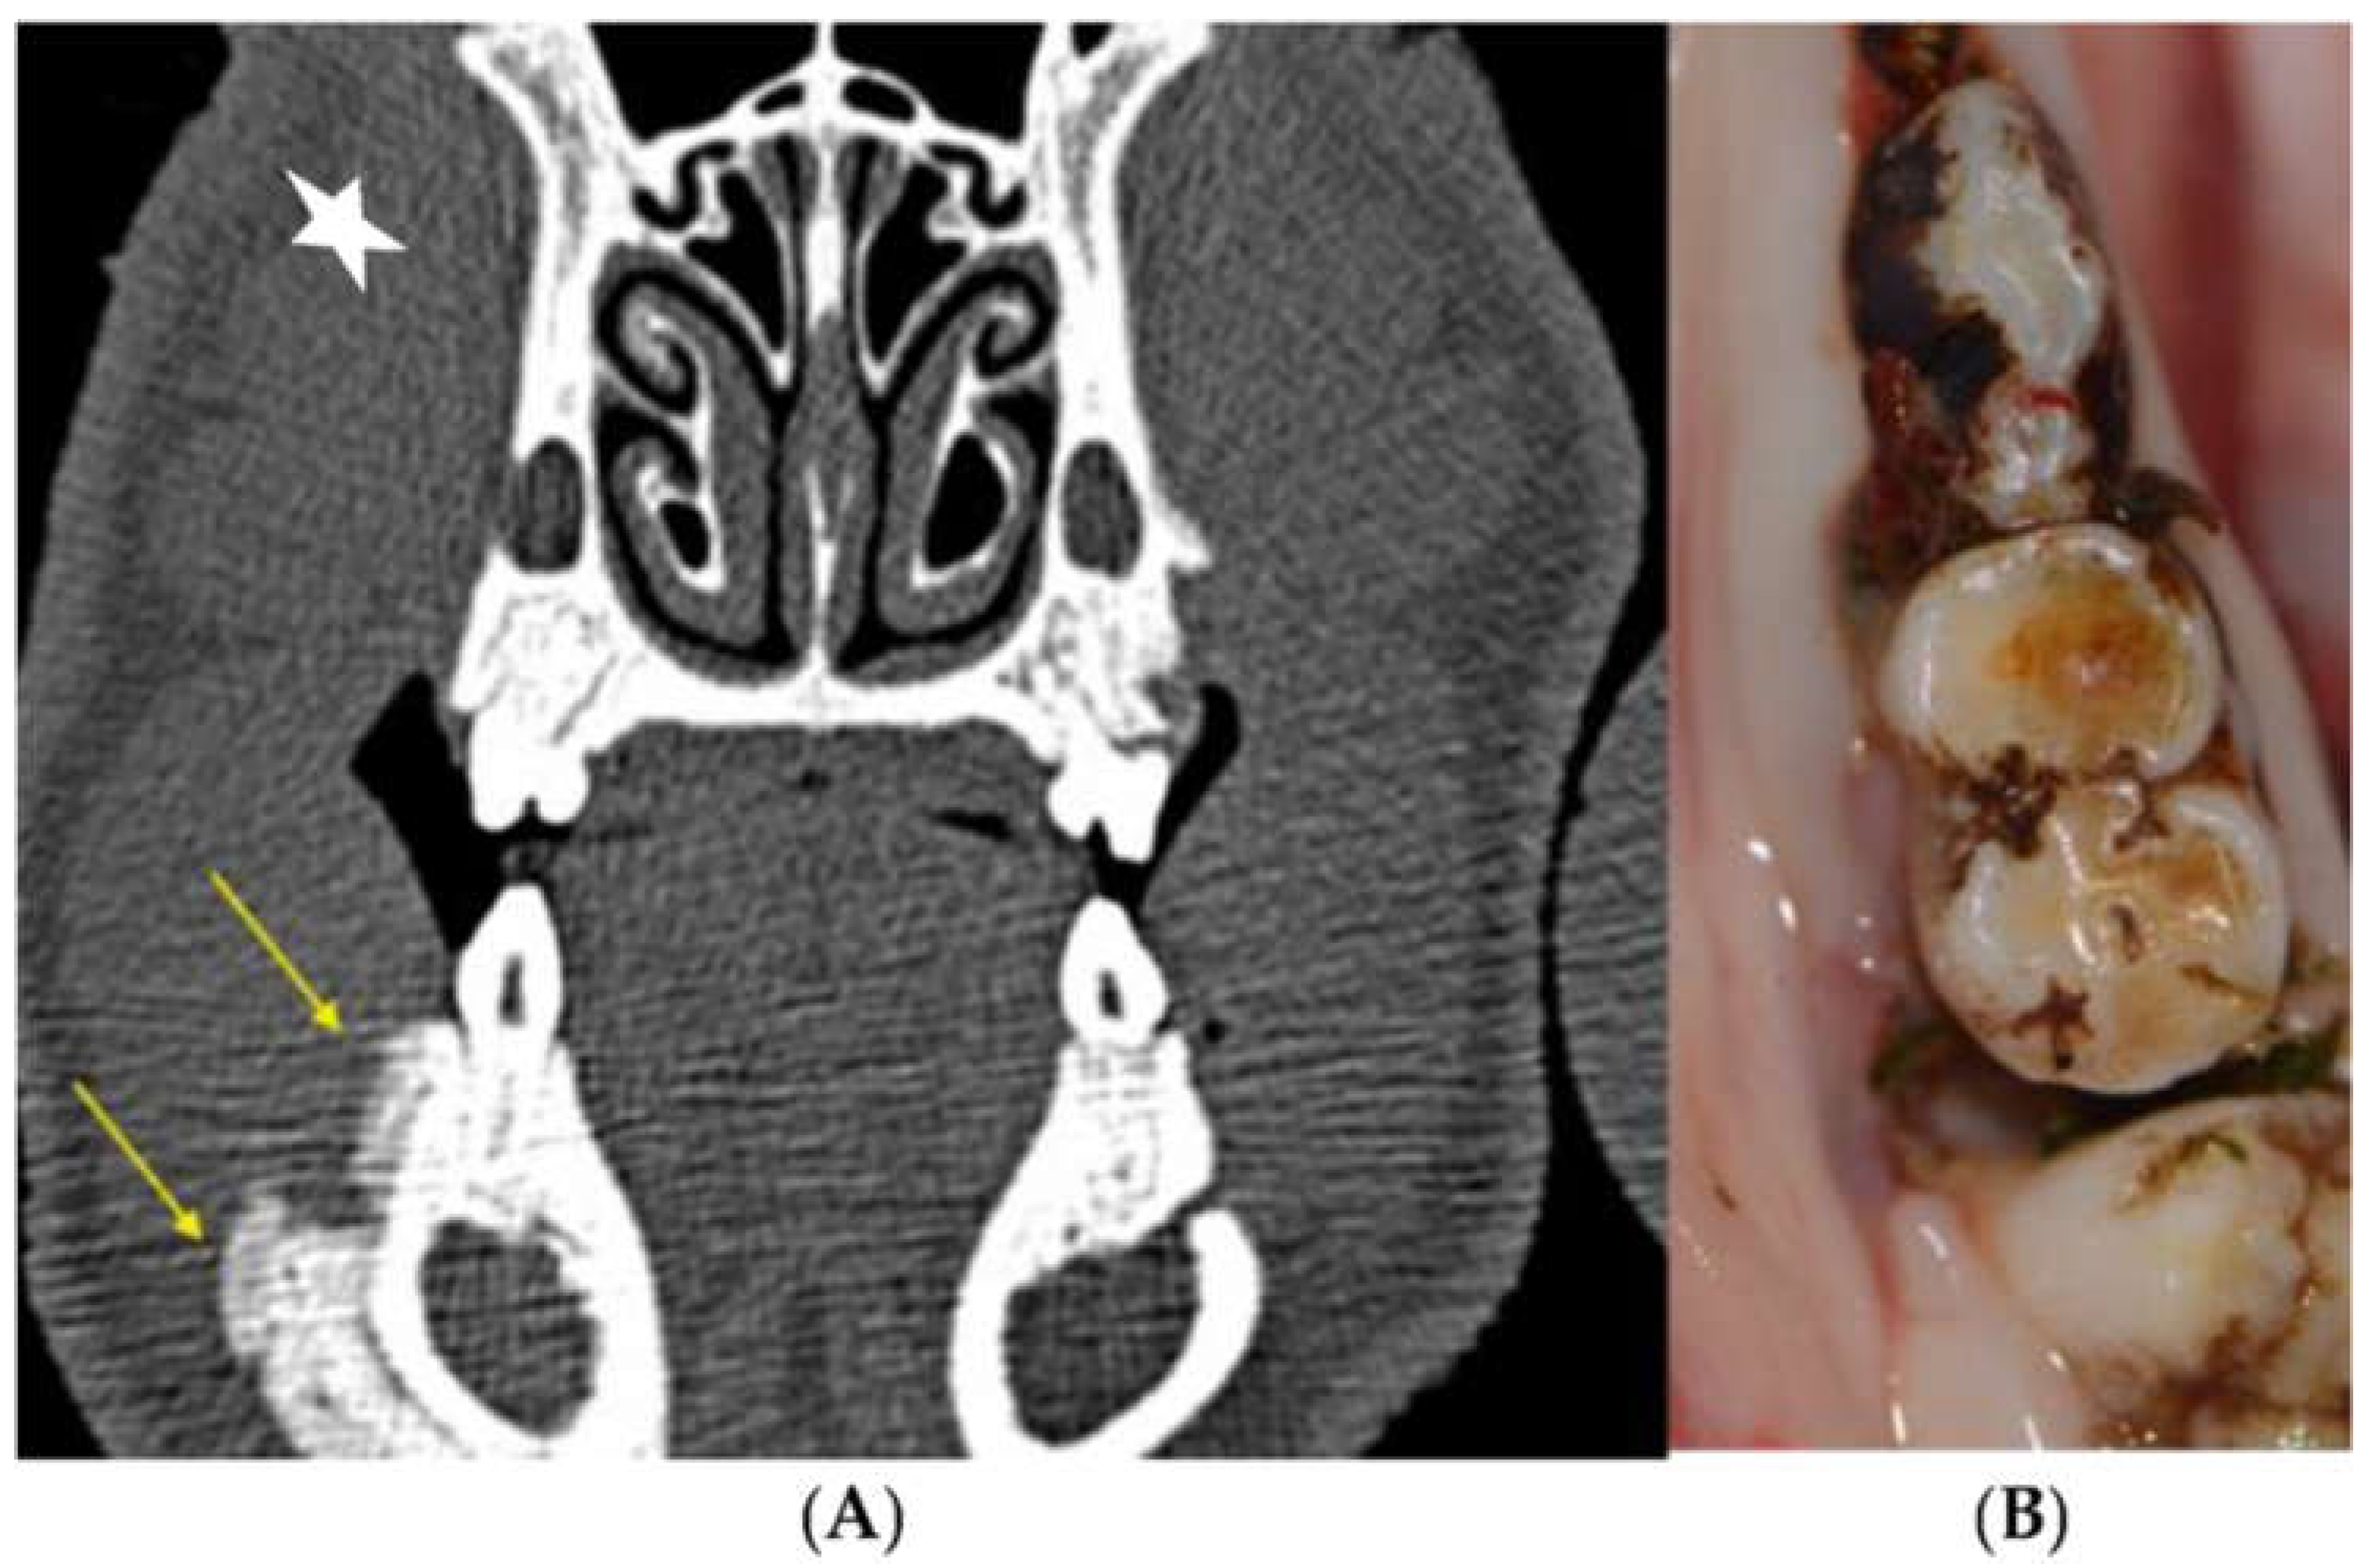

3.2.1. Clinical Evaluation

3.2.3. Radiological Evaluation